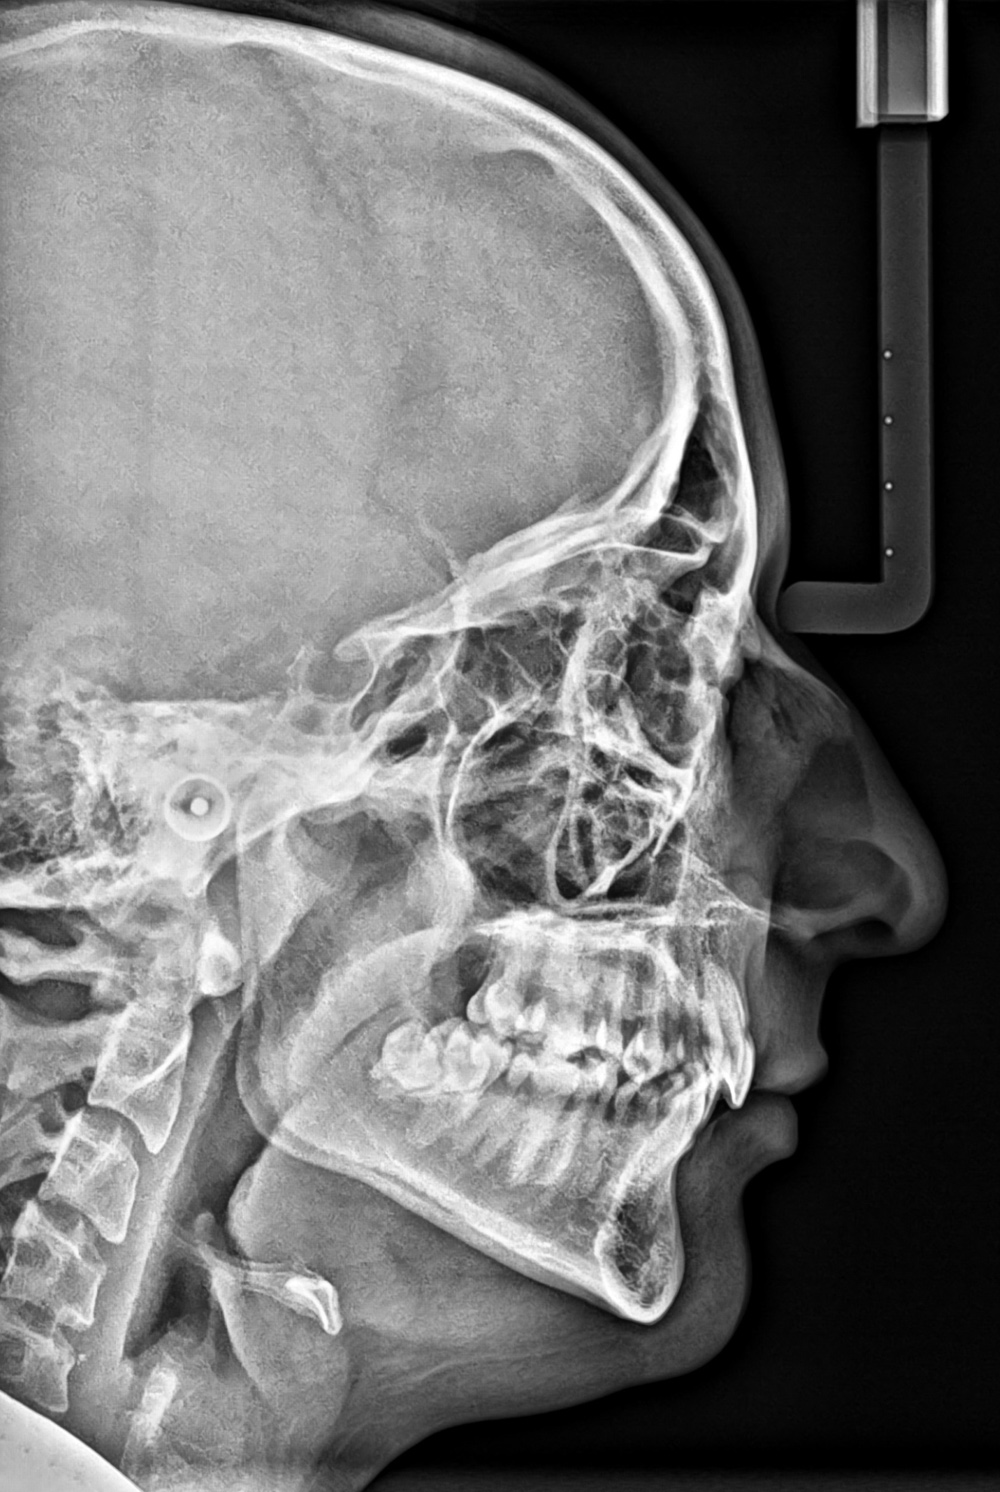

Telerradiografia de perfil;